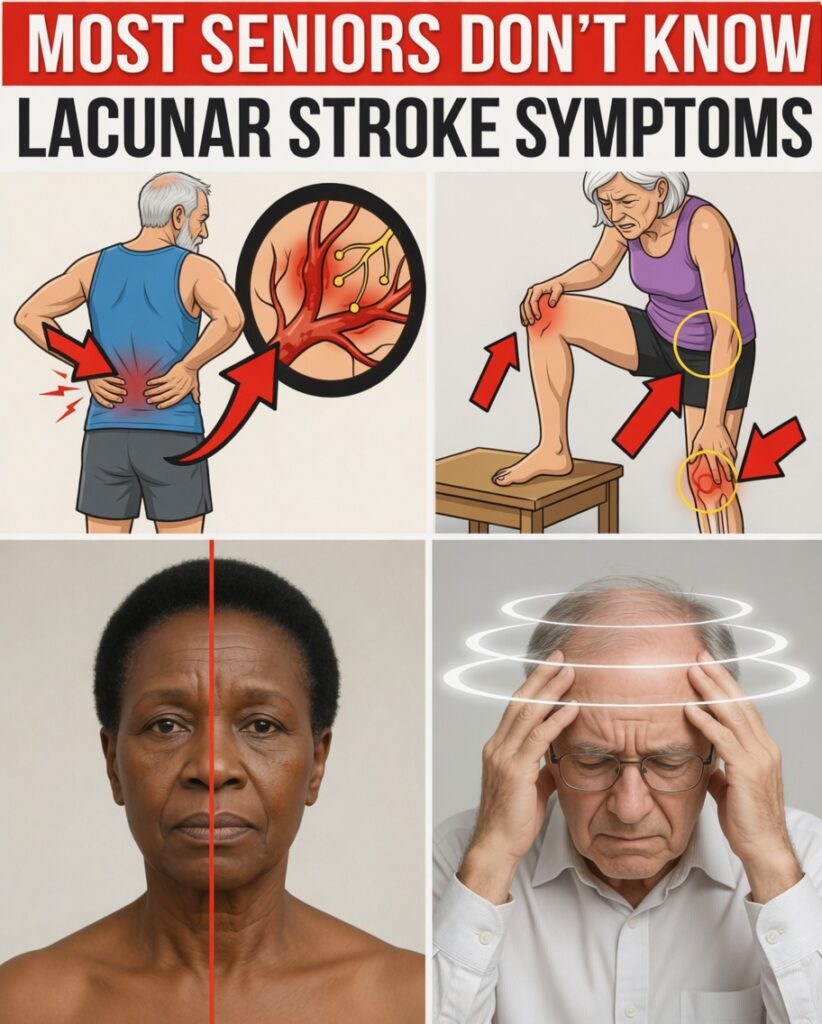

Warning Sign #7: Sudden Burning, Stabbing, or Electric-Shock Pain on One Side

One overlooked lacunar stroke warning sign is sudden, intense pain in one foot, hand, or on one side of the body without any injury. It may feel burning, stabbing, or like an electric shock. Even light contact—such as a bedsheet brushing the skin—can feel unbearable and disrupt sleep.

This type of thalamic pain linked to lacunar strokes is often mistaken for peripheral neuropathy or nerve irritation. That confusion can delay proper evaluation and care.

If you experience new, unexplained, one-sided burning or shock-like pain, note it as a possible lacunar stroke warning sign and mention it to your doctor.

Warning Sign #5: Sudden Weakness or Clumsiness in One Hand or Leg

A classic lacunar stroke warning sign is brief, one-sided weakness or clumsiness. Your hand may suddenly feel heavy, you might fumble with small objects, or your leg could drag slightly for a few minutes. You may blame tiredness, stress, or a “bad day.”

These short-lived motor changes often reflect real disruptions deep in the brain, even if they disappear quickly. Dropping keys, misbuttoning clothes, or stumbling on flat ground are common clues.

Even if these episodes are mild or intermittent, treat them as possible lacunar stroke warning signs and bring them to your doctor’s attention.

Warning Sign #4: Gradually Worsening Balance, Gait Changes, and Unexplained Falls

This is the lacunar stroke warning sign most people ignore, even though loved ones often notice it first.

Lacunar stroke warning signs can cause:

- Shuffling or shorter steps

- Feet that feel “glued” to the floor when starting to walk

- Frequent tripping, near-falls, or unexplained falls

- Turning that feels unsteady or slow

The fear and embarrassment of falling can make you avoid outings, social events, or exercise—shrinking your world little by little.

This lower-body movement pattern, often called vascular parkinsonism, is misattributed to arthritis or “just aging” in roughly 90% of cases. Yet it frequently reflects damage from lacunar strokes affecting deep brain circuits.

Warning Sign #1: Brief Episodes of Confusion or Mental Fog

Short bursts of confusion or disorientation can also signal lacunar stroke warning signs. Examples include:

- Feeling suddenly unsure of where you are or what you were doing

- A few minutes of “blanking out” or not thinking clearly

- Difficulty finding words or following what someone is saying, then quickly returning to normal

Even if these episodes are brief and you recover fully, they can reflect activity in deeper brain regions affected by lacunar strokes. Because they pass quickly, many people ignore them.

Any new, unexplained spells of confusion or mental fog should be treated as potential lacunar stroke warning signs and discussed promptly with a healthcare professional.